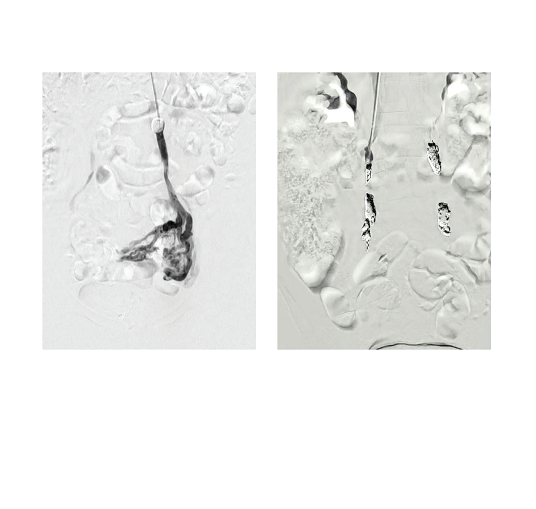

Winokur-Fig1-CLD-MarchApril 2026

Figure 1. Pre and post pelvic vein embolization.